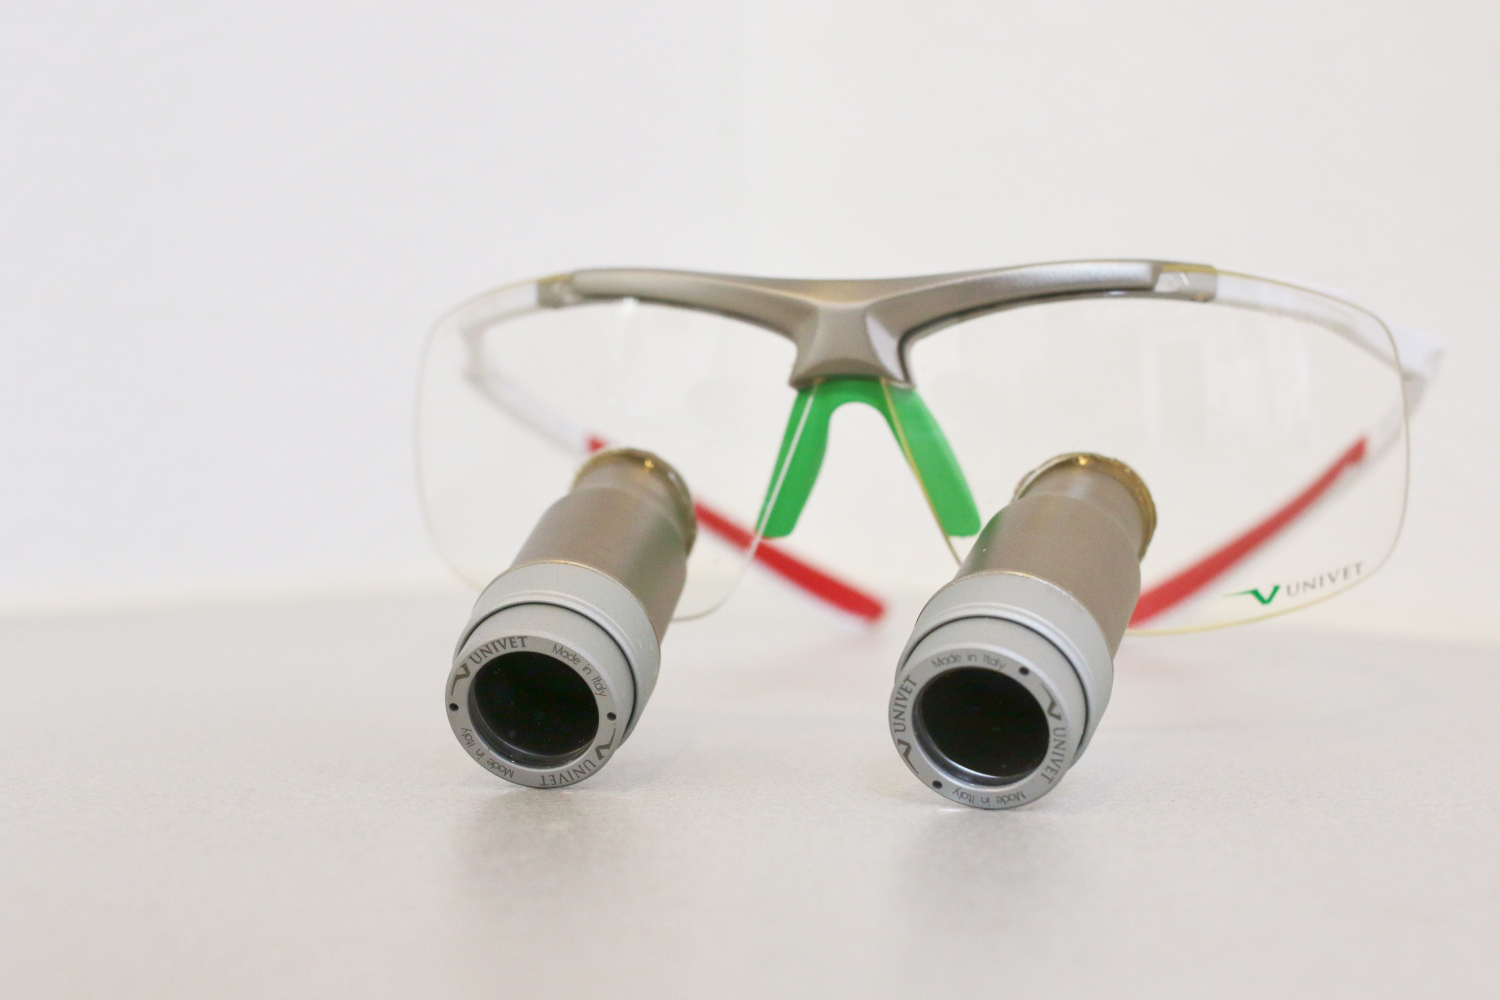

歯科用拡大鏡

歯を削る・根の治療・外科手術などを行うときには、よりしっかり自分の目で見えるようにするために、拡大鏡を使用しています。肉眼では確認することが困難な、歯の小さな凹凸やひび割れなどを判別できます。視野を拡大することで繊細でより丁寧な診療に役立ちます。治療の精度を上げることで、歯の寿命を延ばすために使用します。